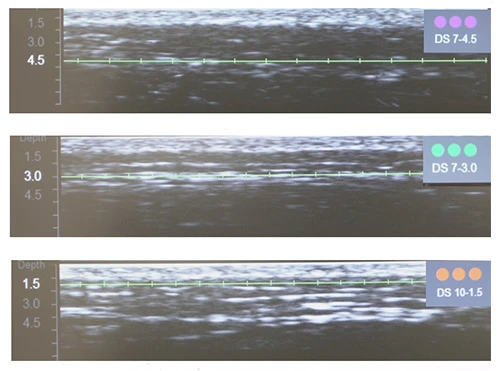

Диагностическая визуализация щёчной, периоральной и периорбитальной зон

Диагностическая визуализация щёчной, периоральной и периорбитальной зон. Протокол лечения: DS 7–4,5 70 линий; DS 7–3,0 402 линии; DS 10–1,5 192 линии. Суммарно все лицо: 850 линий.